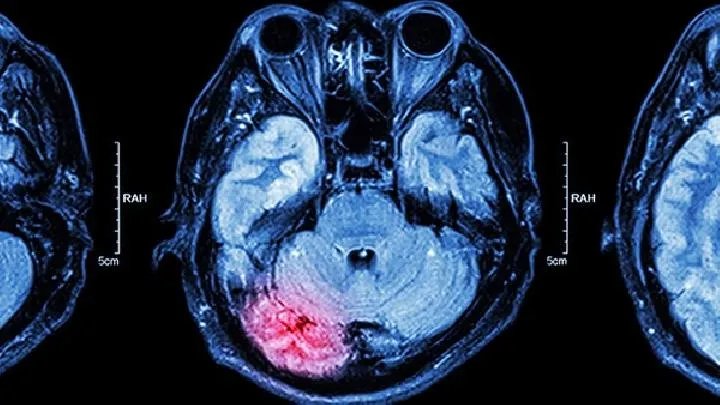

小儿脑瘫的早期症状表现有哪些